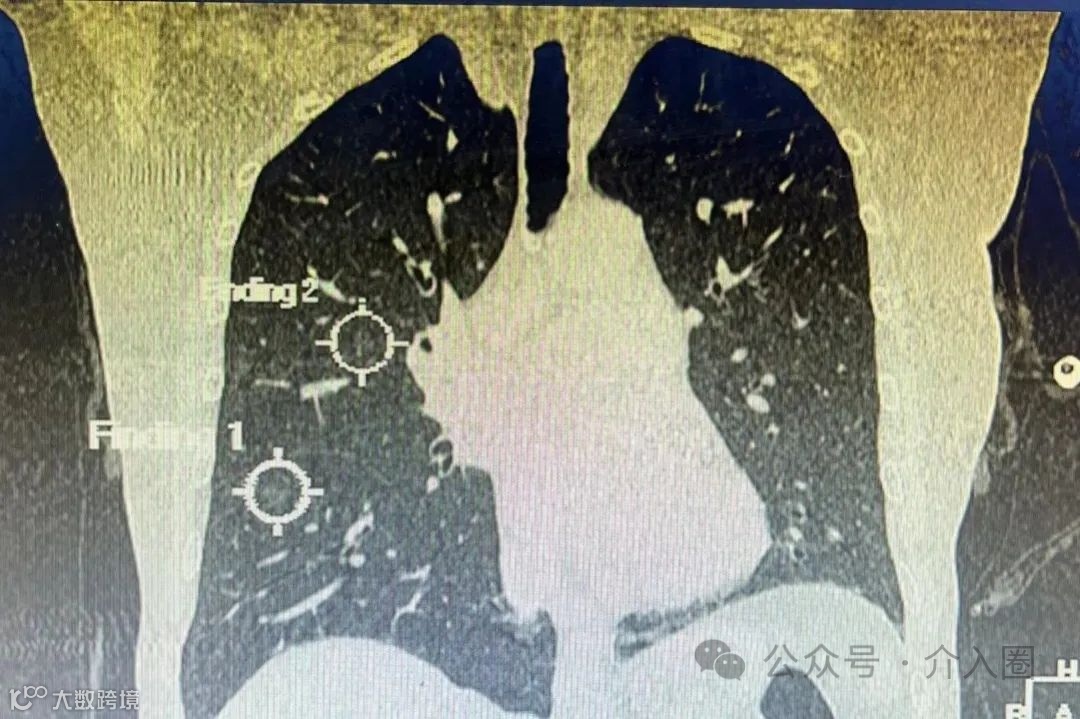

患者情况:69岁,女性,出现胸闷偶伴咳嗽,持续至今仍未好转,影像检查结果提示,患者双肺多处有磨玻璃样结节,直径近1厘米。